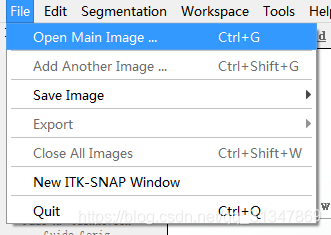

选择 File -> Open Main Image